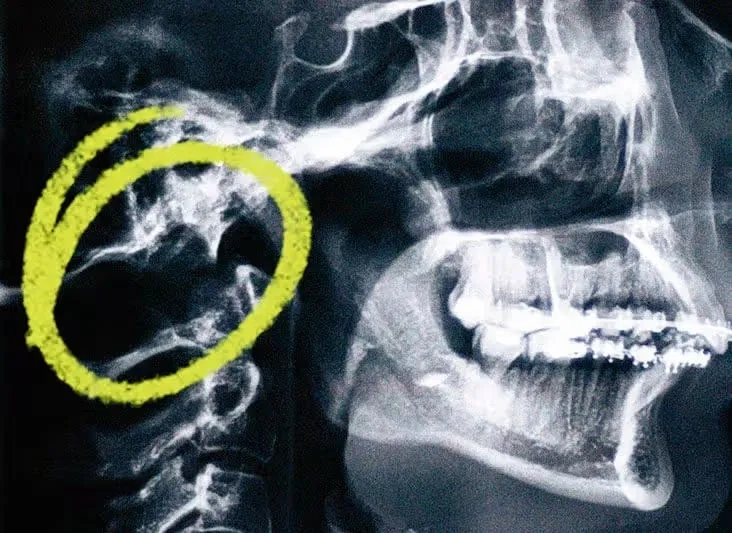

The top Chiari Malformation images everyone is searching for

Decompression surgery for Chiari malformation